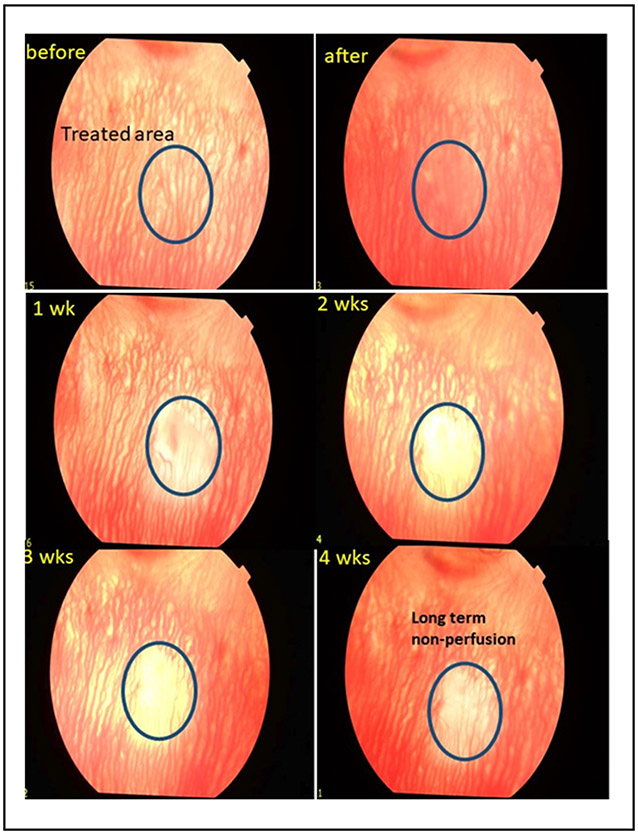

PUT treatment was also performed of normal choroidal vasculature. To remove normal choroidal vasculature, the laser fluence was increased from 30 to 75 mJ/cm2 (Fig. 3).

Figure 3.

Fundus photography of the choroidal vasculature at baseline, immediately after, and weekly for 4 weeks after PUT treatment demonstrating removal of the choroidal microvasculature in the treated area that persists with long term non-perfusion at 4 weeks.

Treatment of choroidal vasculature was performed in normal rabbits (without intravitreal injection) using laser fluence of 75 mJ/cm2, ultrasound of 2MPa with a total of 15 minutes of treatment. Fundus images demonstrates immediately a haziness to the choroidal vascular wall followed by removal of the choroidal vasculature that persisted to 4 weeks and resulted in long-term non-perfusion of the choroidal vasculature to 4 weeks. The treatment of the choroidal vasculature necessitated the use of higher laser fluence, ultrasound, and treatment duration than required for treatment of angiogenesis, suggesting that lower PUT treatment could selectively remove neovascularization without damaging the normal vasculature. These results suggested that PUT could result in selective removal of angiogenesis in the treated area without damaging the surrounding normal retinal and choroidal structure.